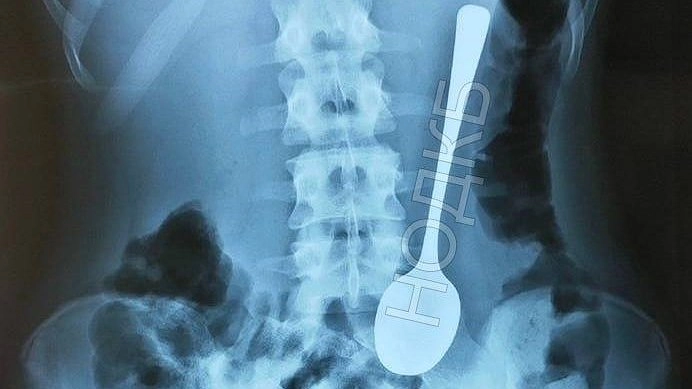

Ребенок проглотил чайную ложку в Нижнем Новгороде

Нижегородский врач-эндоскопист, заведующий отделением НОДКБ Александр Дворянинов извлек из желудка ребенка проглоченную им чайную ложку. Об этом сообщает в Telegram представитель сферы здравоохранения Алексей Никонов.

Когда эндоскописту позвонили хирурги и рассказали про ребенка с десертной ложкой в желудке, который ожидает в приемном покое, Александр Дворянинов сначала принял это за шутку. Однако это оказалось правдой.

Врач аккуратно извлек инородное тело с помощью гастроскопа. Ребенку даже не потребовалось давать наркоз. Медсестры, которые давно работали в больнице, отметили, что таких случаев больше не было. Сейчас ложка заняла место в музее инородных тел НОДКБ.